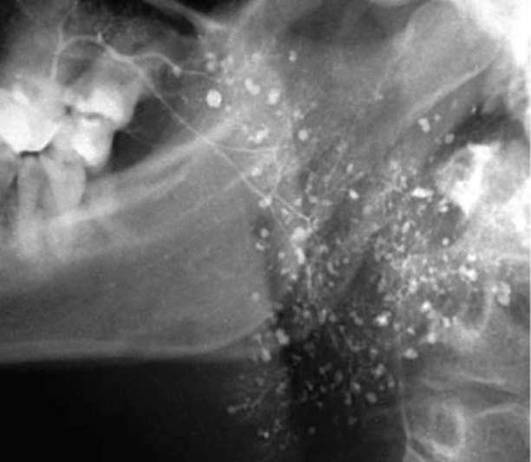

Диагностика. В распознавании слюннокаменной болезни имеет значение не только обнаружение камня, но и выявление причины камнеобразования. Анамнестический признак в виде слюнной колики в 99% случаев позволяет предположить наличие конкремента. На обзорных рентгенограммах рентгеноконтрастные камни хорошо визуализируются (рис. 6.11-6.13), на сиалограммах они видны в виде очага дефекта наполнения контрастного вещества. На эхосиалограммах камни видны по типу «звуковой дорожки». Особенно часто (более чем в 99%) камни выявляются на компьютерных томограммах.

image

Рис. 6.12. Рентгенограмма нижней челюсти в боковой проекции. В области левой поднижнечелюстной железы определяется конкремент

Рис. 6.13. Рентгенограмма в проекции дна полости рта. В правой подъязычной области определяется камень